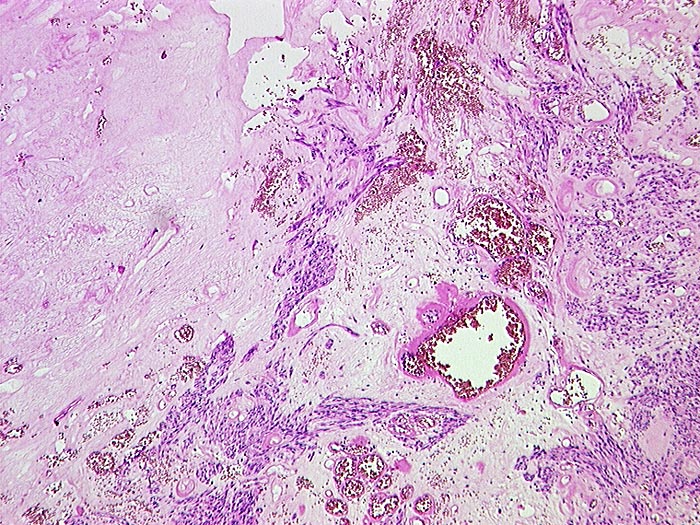

Makroskopisch imponieren kleine Tumoren als peritoneale, intramurale oder submuköse Knoten. Grössere Tumoren wölben sich oft vor und können ulzerieren. Die Schnittfläche ist weisslich und kann Einblutungen, Zysten, Fibroseareale oder Nekrosen aufweisen. Histologisch werden Spindelzelltyp (70%), Epitheloidzelltyp (20%) oder gemischtzelliger Typ (10%) unterschieden. Der histologische Subtyp scheint keinen Zusammenhang mit zugrundeliegender Mutation, Therapieansprechen und Prognose zu haben. Gelegentlich sind vor allem die kleineren Tumoren zellarm und kollagenreich.

• Herdförmig pseudozystische Auflockerung des Tumorgewebes.